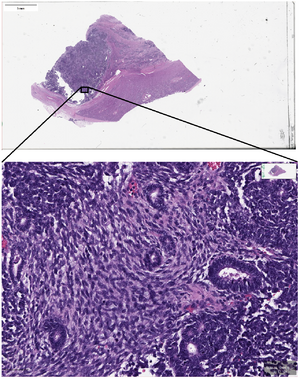

Trained pathologists traditionally view tissue slides under a microscope. These tissue slides may be stained to highlight cellular structures. When slides are digitized, they are able to be shared through tele-pathology and are numerically analyzed using computer algorithms. Algorithms can be used to automate the manual counting of structures, or for classifying the condition of tissue such as is used in grading tumors. They can additionally be used for feature detection of mitotic figures, epithelial cells, or tissue specific structures such as lung cancer nodules, glomeruli, or vessels, or estimation of molecular biomarkers such as mutated genes, tumor mutational burden, or transcriptional changes.[15][16][17] This has the potential to reduce human error and improve accuracy of diagnoses. Digital slides can be easily shared, increasing the potential for data usage in education as well as in consultations between expert pathologists. Multiplexed imaging (staining multiple markers on the same slide) allows pathologists to understand finer distribution of cell-types and their relative locations.[18] An understanding of the spatial distribution of cell-types or markers and pathways they express, can allow for prescription of targeted drugs or build combinational therapies in a personalized manner.

- Figure 2 - available via license: Creative Commons Attribution 4.0 International - ^ "FDA allows marketing of first whole slide imaging system for digital pathology" (Press release). FDA. April 12, 2017. Retrieved May 24, 2017.